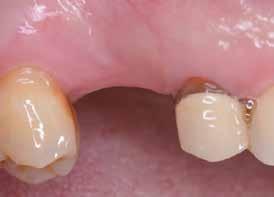

Preoperatív helyzet

Egy fiatal páciens jelentkezett nálunk, akinek eltörött a szabad véggel rendelkező hídja (1. ábra). A hiányzó, első premoláris fog esetén implantációs pótlást javasoltunk. A csontállomány értékeléséhez CBCT-vizsgálatot végeztünk, és az elemzéséhez NNT Viewert (NewTom) használtunk, és copaSKY 4×10 mm-es (bredent medical) implantátumot választottuk a fog pótlásához

1. ábra: Műtét előtti fogászati panorámafelvétel, amelyen a hiányzó felső állcsont jobb első premolárisát és a szabad véggel rendelkező hidat láthatjuk. — 2. ábra: Az implantátum méreteinek megtervezése CBCT-vel. 3. ábra: Bukkális lágyrészdefektus. — 4. ábra: A biológiai szélesség értékelése a vertikális lágyszövetvastagság alapján. 5. ábra: Palatinális „tekercslebeny” – Palatal roll flap. — 6. ábra: Bredent medical copaSKY 4x10 implantátumbeültetés. 7. ábra: Szubkresztális implantátumbeültetés a várható biológiai szélességnek megfelelően.

(2. ábra). A lágyszövetek értékelése Seibert szerinti I. osztályú csontdefektust állapított meg (3. ábra), ezért a beavatkozáskor palatinális „tekercslebenyt” preparáltunk (palatal roll flap), és implantációt végeztünk, hogy kompenzálni tudjuk a bukkális lágyszövet-behúzódást. Megmértük a vertikális lágyszövetvastagságot, és úgy terveztük, hogy a szubkresztális implantátum beültetése összhangban legyen a biológiai szélesség kialakulásával a transzgingivális gyógyulási periódus alatt (4. ábra)